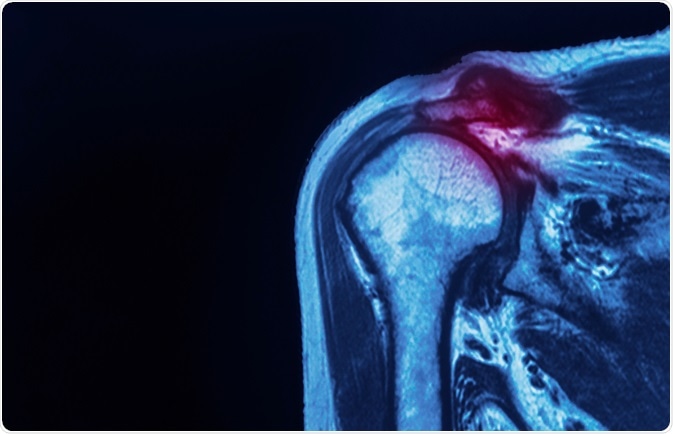

rotator cuffMRI of a human shoulder, with rotator cuff, highlighted. Image Credit: Peter Porrini / Shutterstock.com

Examination may demonstrate atrophy around the shoulder girdle secondary to chronic disuse, most often in the supraspinatus and infraspinatus fosse. Multiple imaging modalities such as radiography, ultrasound and magnetic resonance imaging are used to properly assess the status of the rotator cuff.